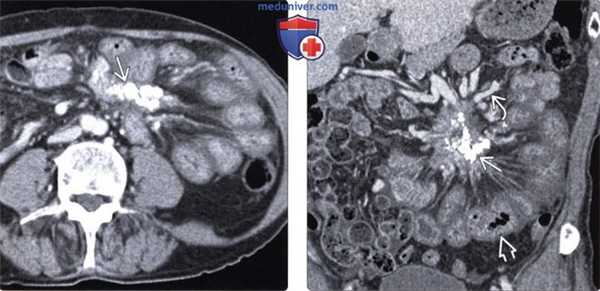

(Слева) На аксиальной КТ с контрастным усилением определяется объемное образование брыжейки инфильтративного характера, вовлекающее брыжеечные сосуды. Обратите внимание на застойные изменения брыжеечных вен. Все это признаки склерозирующего мезентерита.

(Справа) На аксиальной КТ с контрастом у пожилой женщины с болевой симптоматикой и диареей определяется мягкотканное объемное образование в основании брыжейки тонкой кишки, окружающее и сдавливающее брыжеечные сосуды. После биопсии был подтвержден диагноз фиброзирующего мезентерита.

(Слева) На аксиальной КТ с контрастным усилением визуализируется кальцинированное объемное образование в левом верхнем квадранте брыжейки, стягивающее петли кишечника.

(Справа) На корональной КТ с контрастом у этого же пациента определяется обызвествленное объемное образование. Обратите внимание на венозные коллатерали, сформировавшиеся в результате обструкции верхней брыжеечной вены, а также диффузное утолщение стенки тонкой кишки из-за обструкции венозных/лимфатических сосудов. В данном случае изменения обусловлены гистологически подтвержденным стягивающим мезентеритом.